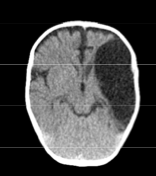

Diagnosis?

Arachnoid Cyst

CT Scan demonstrates a large fluid collection in the left parietal-temporal region. The fluid is the same density as CSF. This scan and history is most consistent with an arachnoid cyst.

The brain tissue looks relatively normal which would make cerebral malformation less likely.

Blood is of a higher density than CSF (acute blood is white, chronic looks slightly darker than brain tissue)